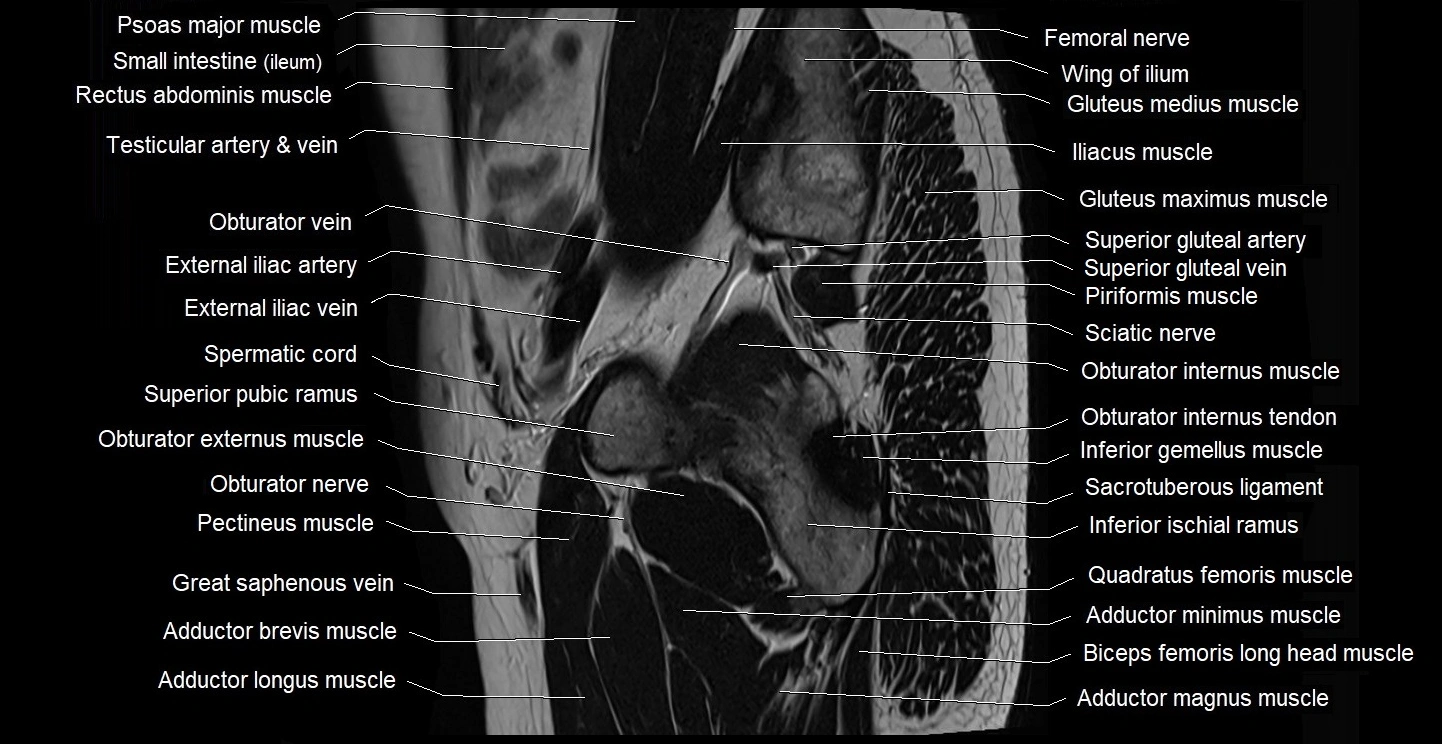

- Adductor brevis muscle

- Adductor longus muscle

- Adductor magnus muscle

- Adductor minimus muscle

- External iliac artery

- External iliac vein

- Femoral nerve

- Gluteus maximus muscle

- Gluteus medius muscle

- Gluteus minimus muscle

- Inferior gemellus muscle

- Inferior gluteal artery

- Obturator externus muscle

- Obturator internus muscle

- Obturator internus tendon

- Obturator nerve

- Obturator vein

- Pectineus muscle

- Piriformis muscle

- Quadratus femoris muscle

- Sacrotuberous ligament

- Sciatic nerve

- Spermatic cord

- Superior gluteal artery

- Superior gluteal veins